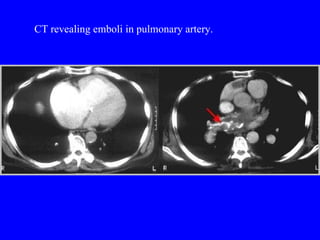

Pulmonary embolism (PE) is a common and potentially fatal condition where blood clots block arteries in the lungs. An estimated 5 million venous thromboses occur annually worldwide, with 10-30% of cases resulting in PE. Risk factors include immobilization, surgery, cancer, and estrogen use. Diagnosis involves assessing clinical probability based on symptoms and risk factors, followed by tests like D-dimer, chest imaging, ultrasound, V/Q scan, CT, or angiogram. Treatment aims to prevent further clotting with anticoagulants like heparin and warfarin, provide supportive care, and in some severe cases utilize thrombolysis or embolectomy.